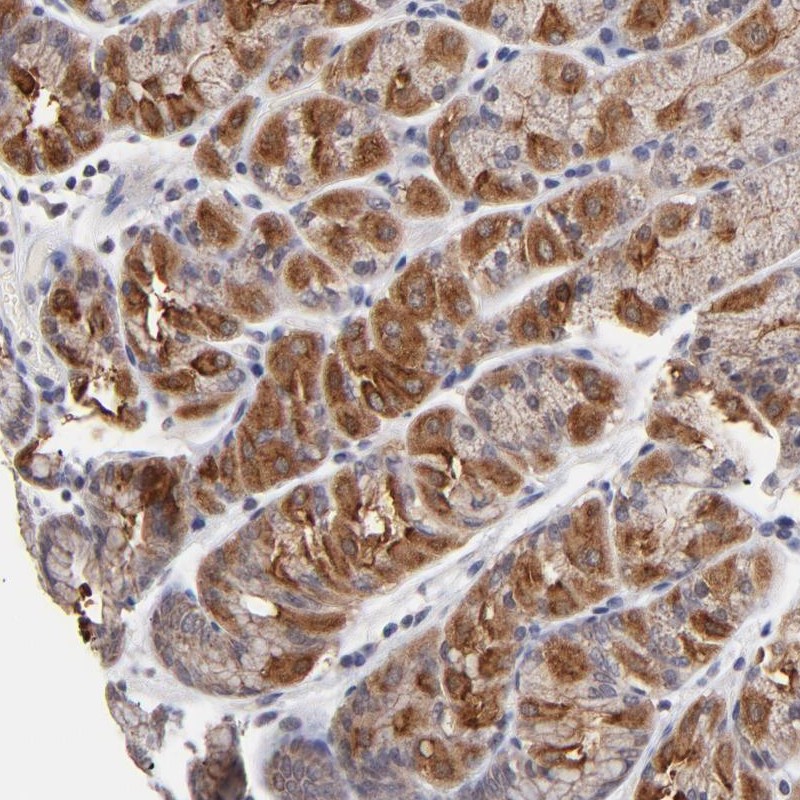

Immunohistochemical staining of human stomach shows strong cytoplasmic positivity in glandular cells.